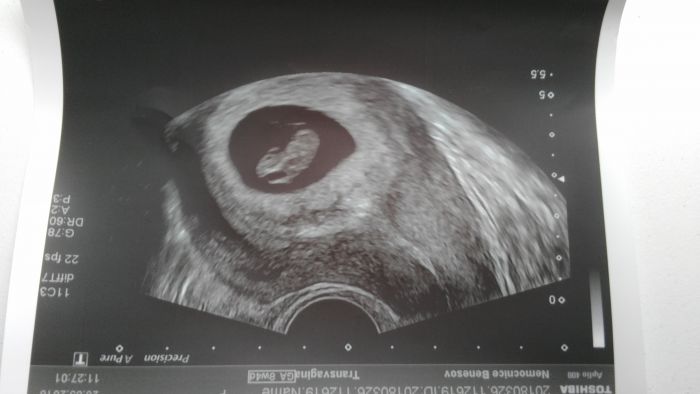

Ja mám jednu už z 5tt, ale tam je vidět pouze 1mm dutinka :D a pak z ko 7+3. Další snad bude teď v úterý :)